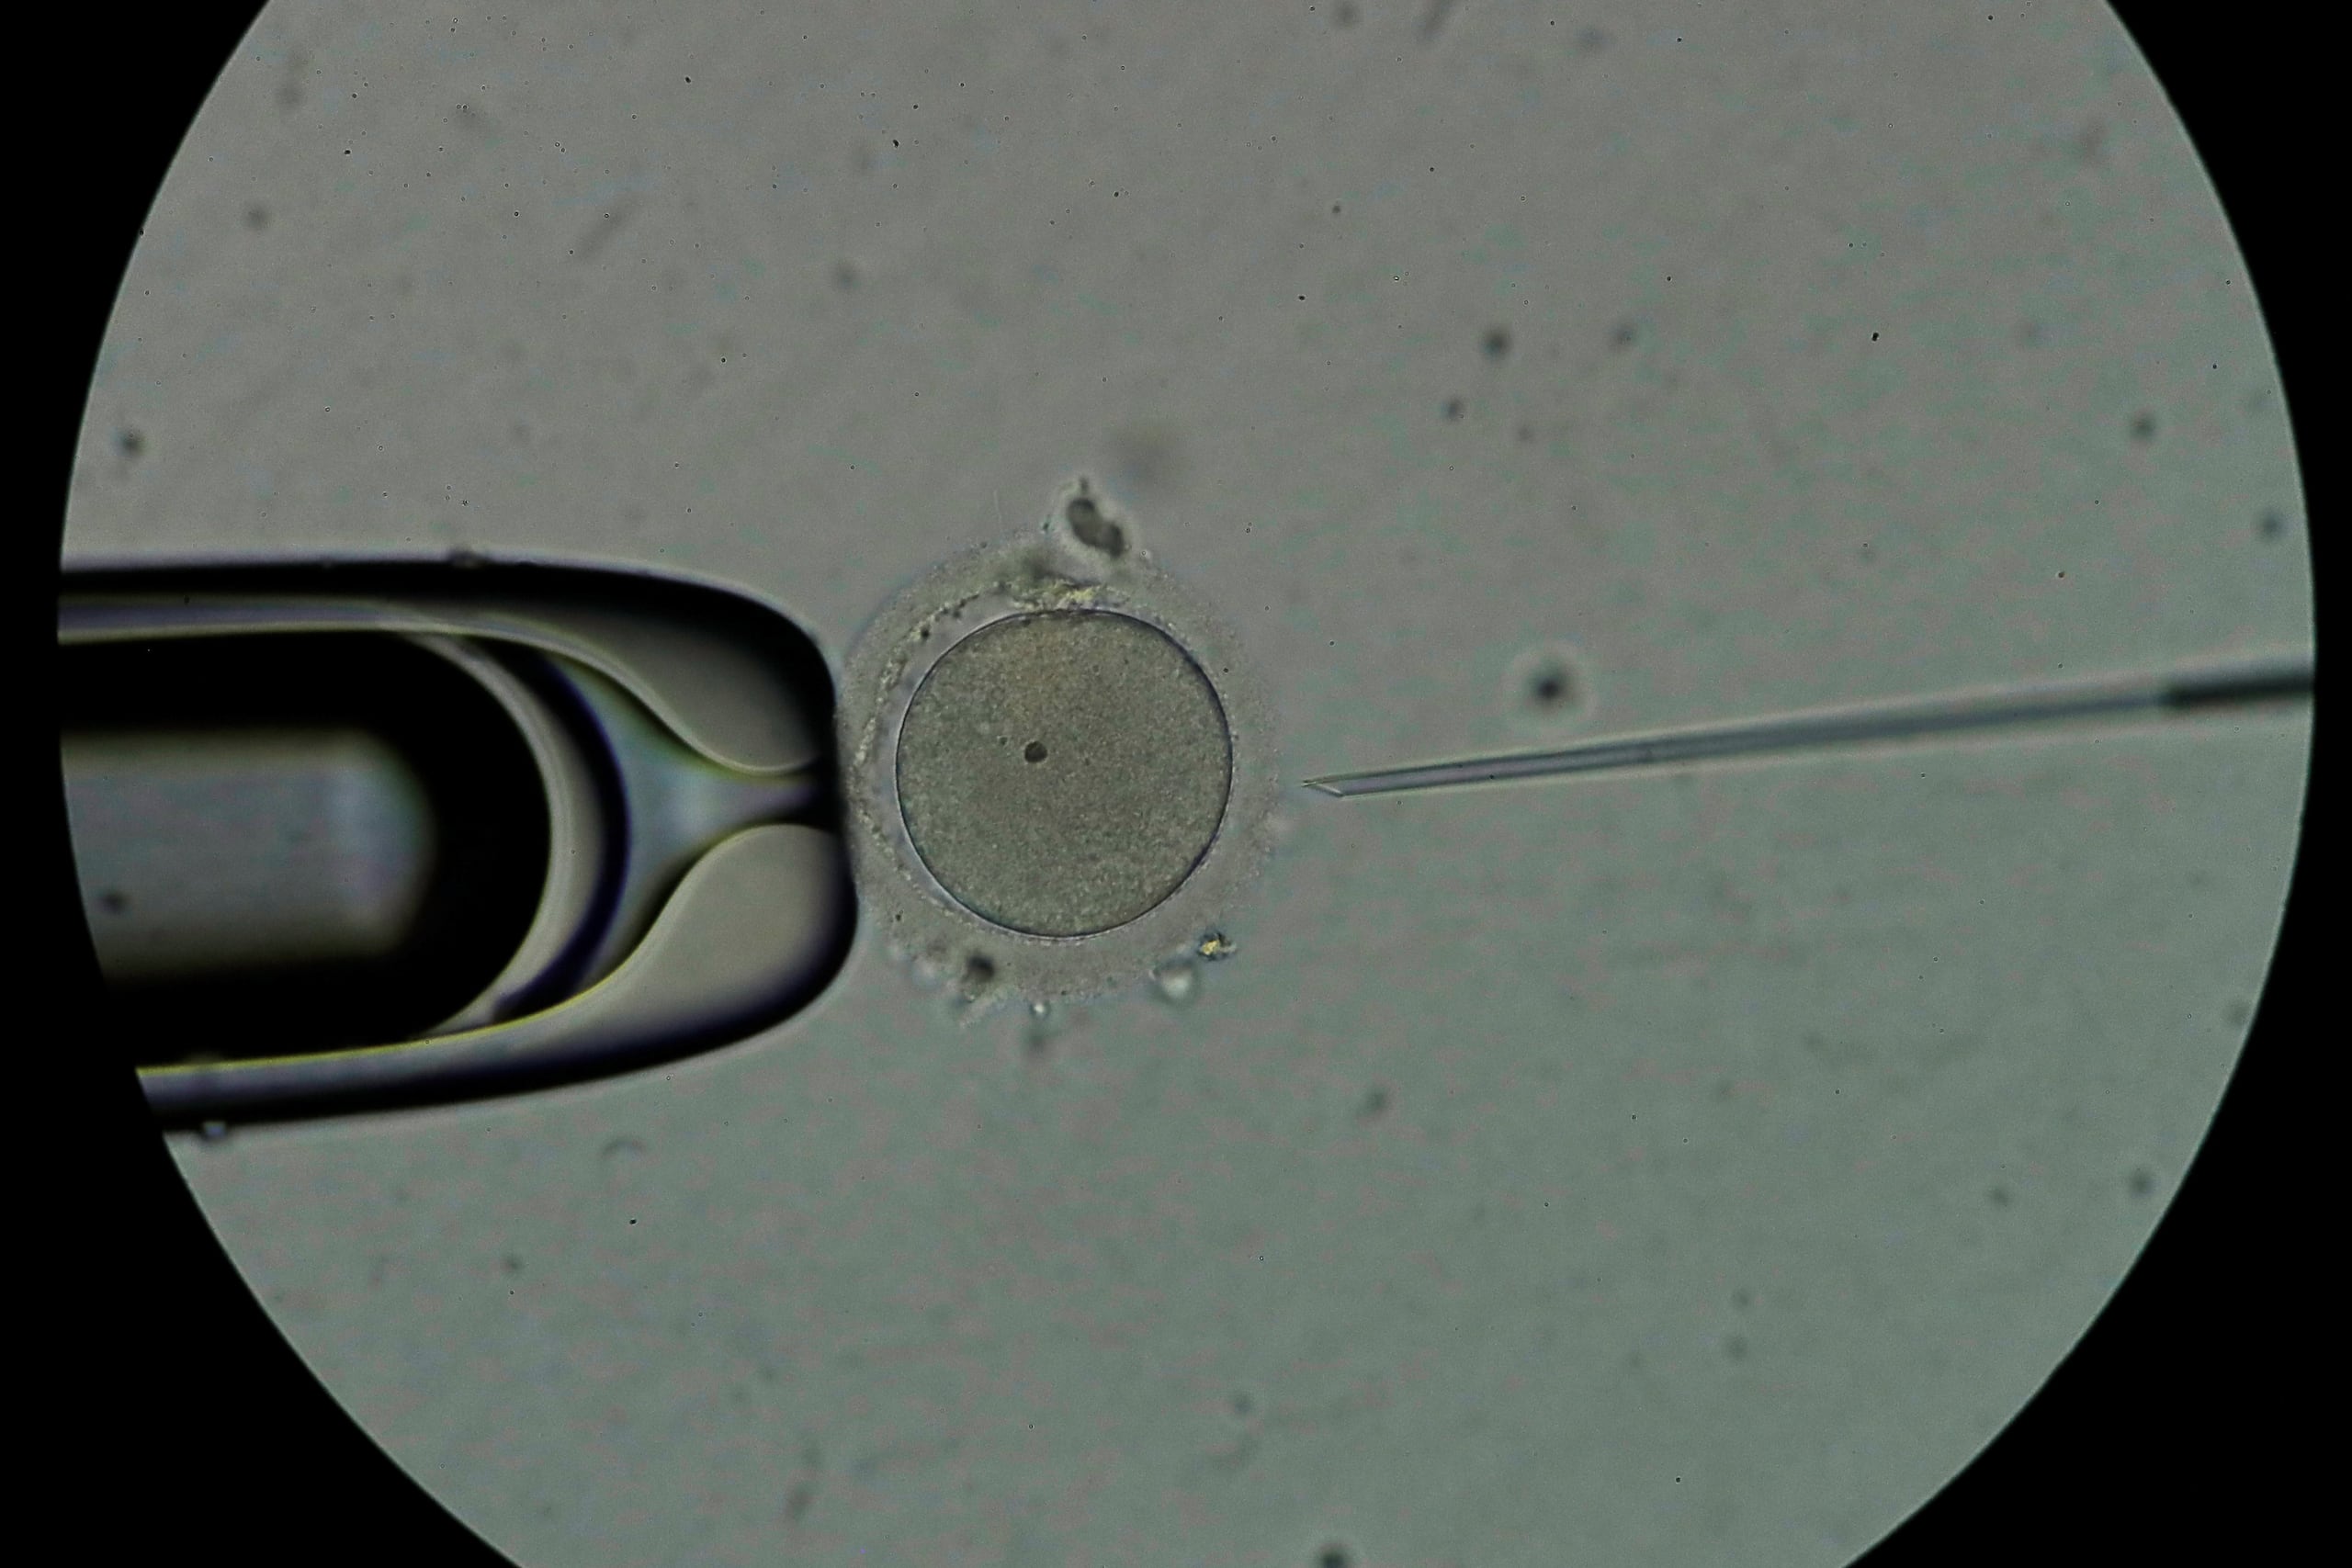

El semen es un líquido jaspeado de color blanquecino y denso que tiene la función principal de facilitar la llegada de los espermatozoides hasta el óvulo con el fin de fecundar, según el portal de salud ‘Cuídate Plus’.

Este está compuesto entre un 1 y 2 por ciento de los espermatozoides y otras células provenientes de los testículos. El resto son secreciones de la próstata, las vesículas seminales, las glándulas de Cowper, las glándulas de Litre, el epidímo, y otros, que crean la parte líquida del semen, el plasma seminal.